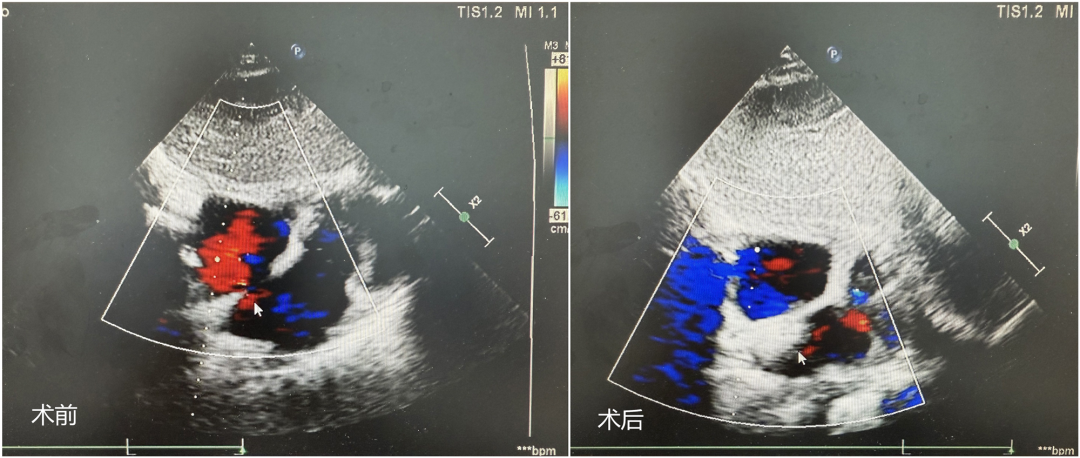

术前、术后心脏超声图像对比。